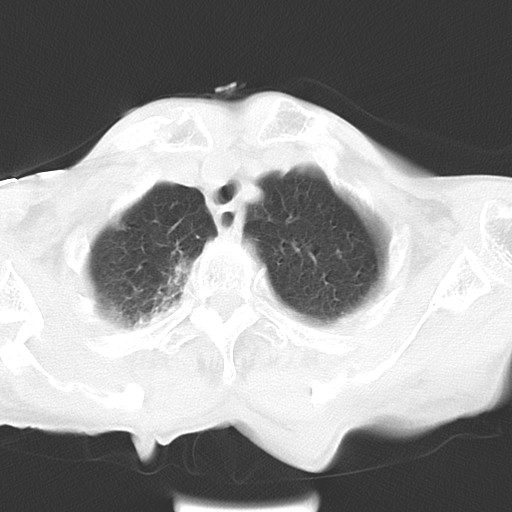

女,93岁,摔伤后检查。

右肺炎症,心功能不全伴双侧胸腔积液,右下肺膨胀不全,食管裂孔疝,冠脉钙化,心包少量积液,左侧肋骨骨折,请上传骨窗.

双肺感染合并双侧胸腔积液、胸膜增厚粘连,骨性胸廓未见明确骨折征。

右侧锁骨\\肩胛骨骨折、右侧湿肺,心功能不全伴双侧胸腔积液,右下肺膨胀不全,左膈破裂或食管裂孔疝,冠脉钙化,心包少量积液,请上传骨窗.

右肺炎症,心功能不全伴双侧胸腔积液,右下肺膨胀不全,食管裂孔疝,冠脉钙化,心包少量积液,左侧肋骨骨折,右肩甲骨粉碎性骨折。93岁,高寿哇!

右肺炎症,心功能不全伴双侧胸腔积液,右下肺膨胀不全,食管裂孔疝,冠脉钙化,心包少量积液,左侧肋骨骨折,右肩甲骨粉碎性骨折。